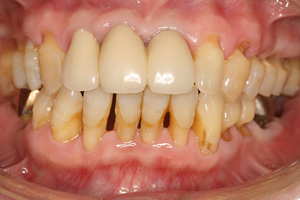

重度歯周病

歯ぐきが大きく下がり、歯槽骨の破壊が著しく進んでいる状態になると重度歯周病と診断されます。歯がグラグラと揺れ、最悪の場合は自然に抜け落ちたり、抜歯を余儀なくされたりします。強い口臭や痛み、膿が出るなどの症状も顕在化することが多く、最終的には歯を抜かなければならないケースもあり、生活の質にも大きな影響が出てきます。

外科的な歯周再生療法や抜歯後のインプラントやブリッジによる補綴治療など、多角的なアプローチが必要です。当院では、重度歯周病の患者さんに対しても、可能なかぎり歯を残す治療に注力しますが、骨の状態によっては抜歯の選択をせざるを得ないケースも存在します。